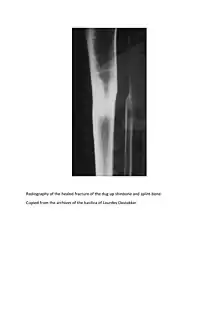

Pieter De Rudder (July 2, 1822 in Jabbeke – March 22, 1898), in many French books Pierre De Rudder, in English Peter De Rudder.[1] His recovery from a broken leg is one of the most famous recognized Lourdes miracles (a bronze cast of his bones is exhibited in the Lourdes Medical Bureau[2]), although it is not supposed to have occurred in Lourdes itself, but in a sanctuary of Our Lady of Lourdes at Oostakker near Ghent (Belgium, East Flanders).